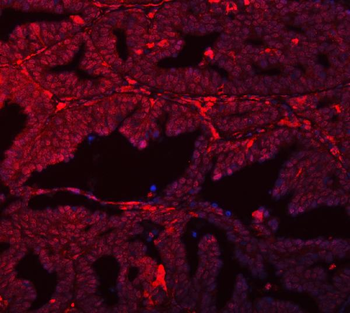

Antibody used in IHC on Human Intestine at 4.0-8.0 ug/ml.